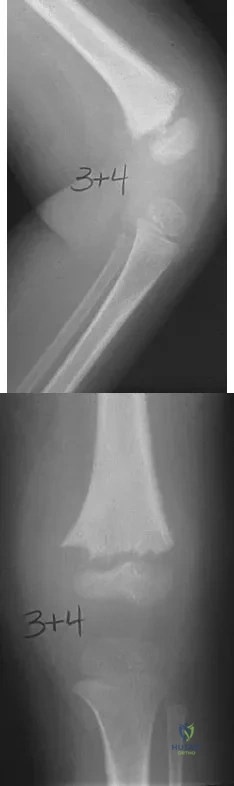

A 55-year-old man sustained an elbow dislocation in a fall. Postreduction radiographs are shown in Figures 40a and 40b. What is the best course of management?

Explanation